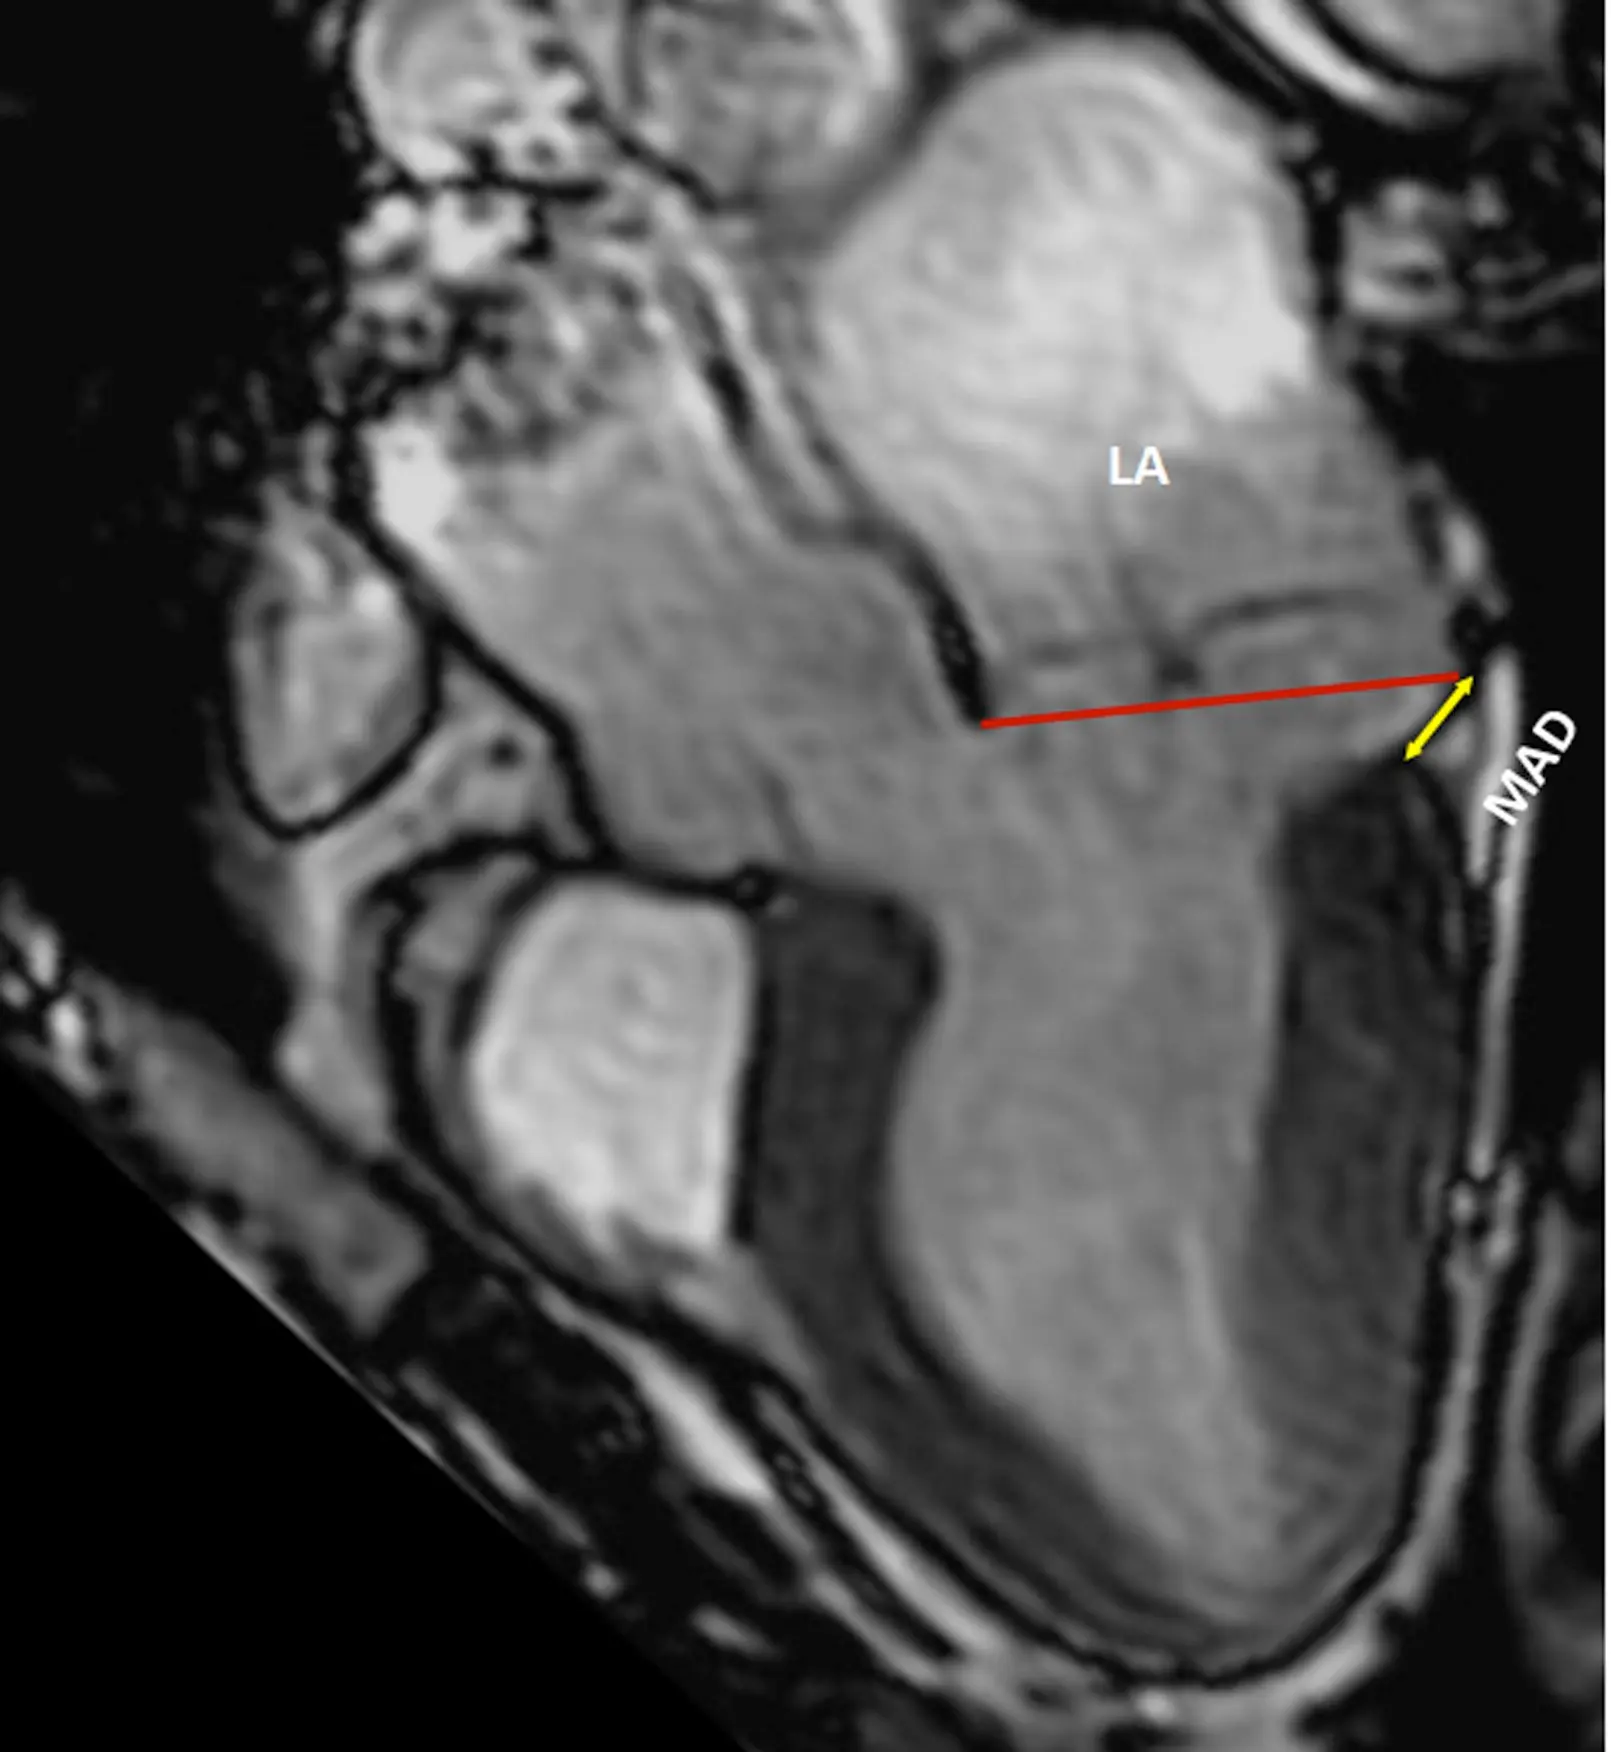

• Mitral Annular Disjunction (MAD)

Mitral Annular Disjunction (MAD)